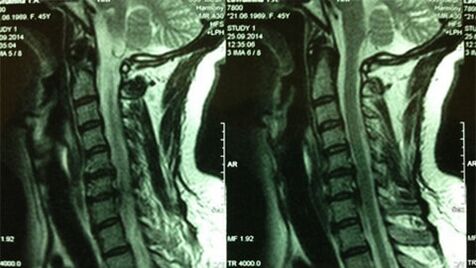

- X -ray cervical department;In the early stages of the process, the cervical department MRI will be more informative - it will ensure high visualization - the quality of solid and soft tissue - will indicate the condition of the intervertebral disc, the presence of osteophytes, deformation, damage to the nerve roots and blood vessels;will assess the state of ligaments, muscles, bone tissue;